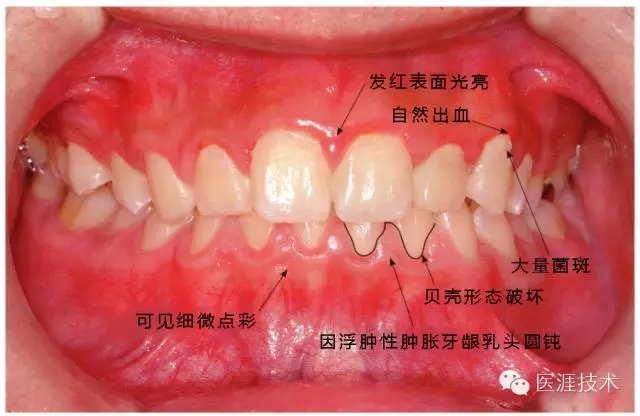

14歲男性牙齦炎的臨床圖像

640.webp (12).jpg

14歲男性。刷牙狀態(tài)不佳。整顎浮腫性發(fā)紅、腫脹且刺激出血。牙頸部有早期齲(白斑)。